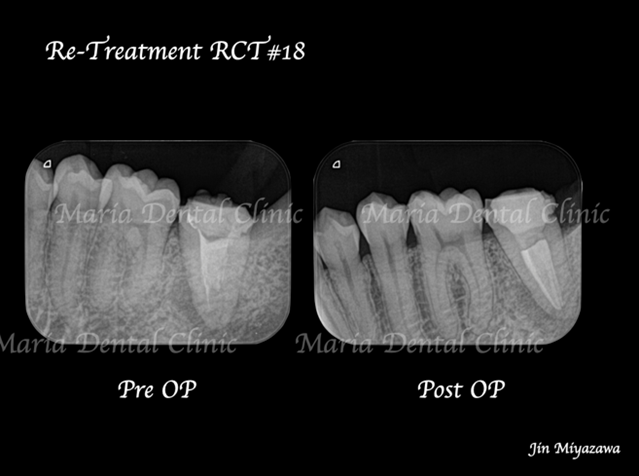

• 目白マリア歯科1214再根管治療症例ビフォーアフター

2019.12.14

【症例】再根管治療| CT、マイクロスコープを使った精密根管治療